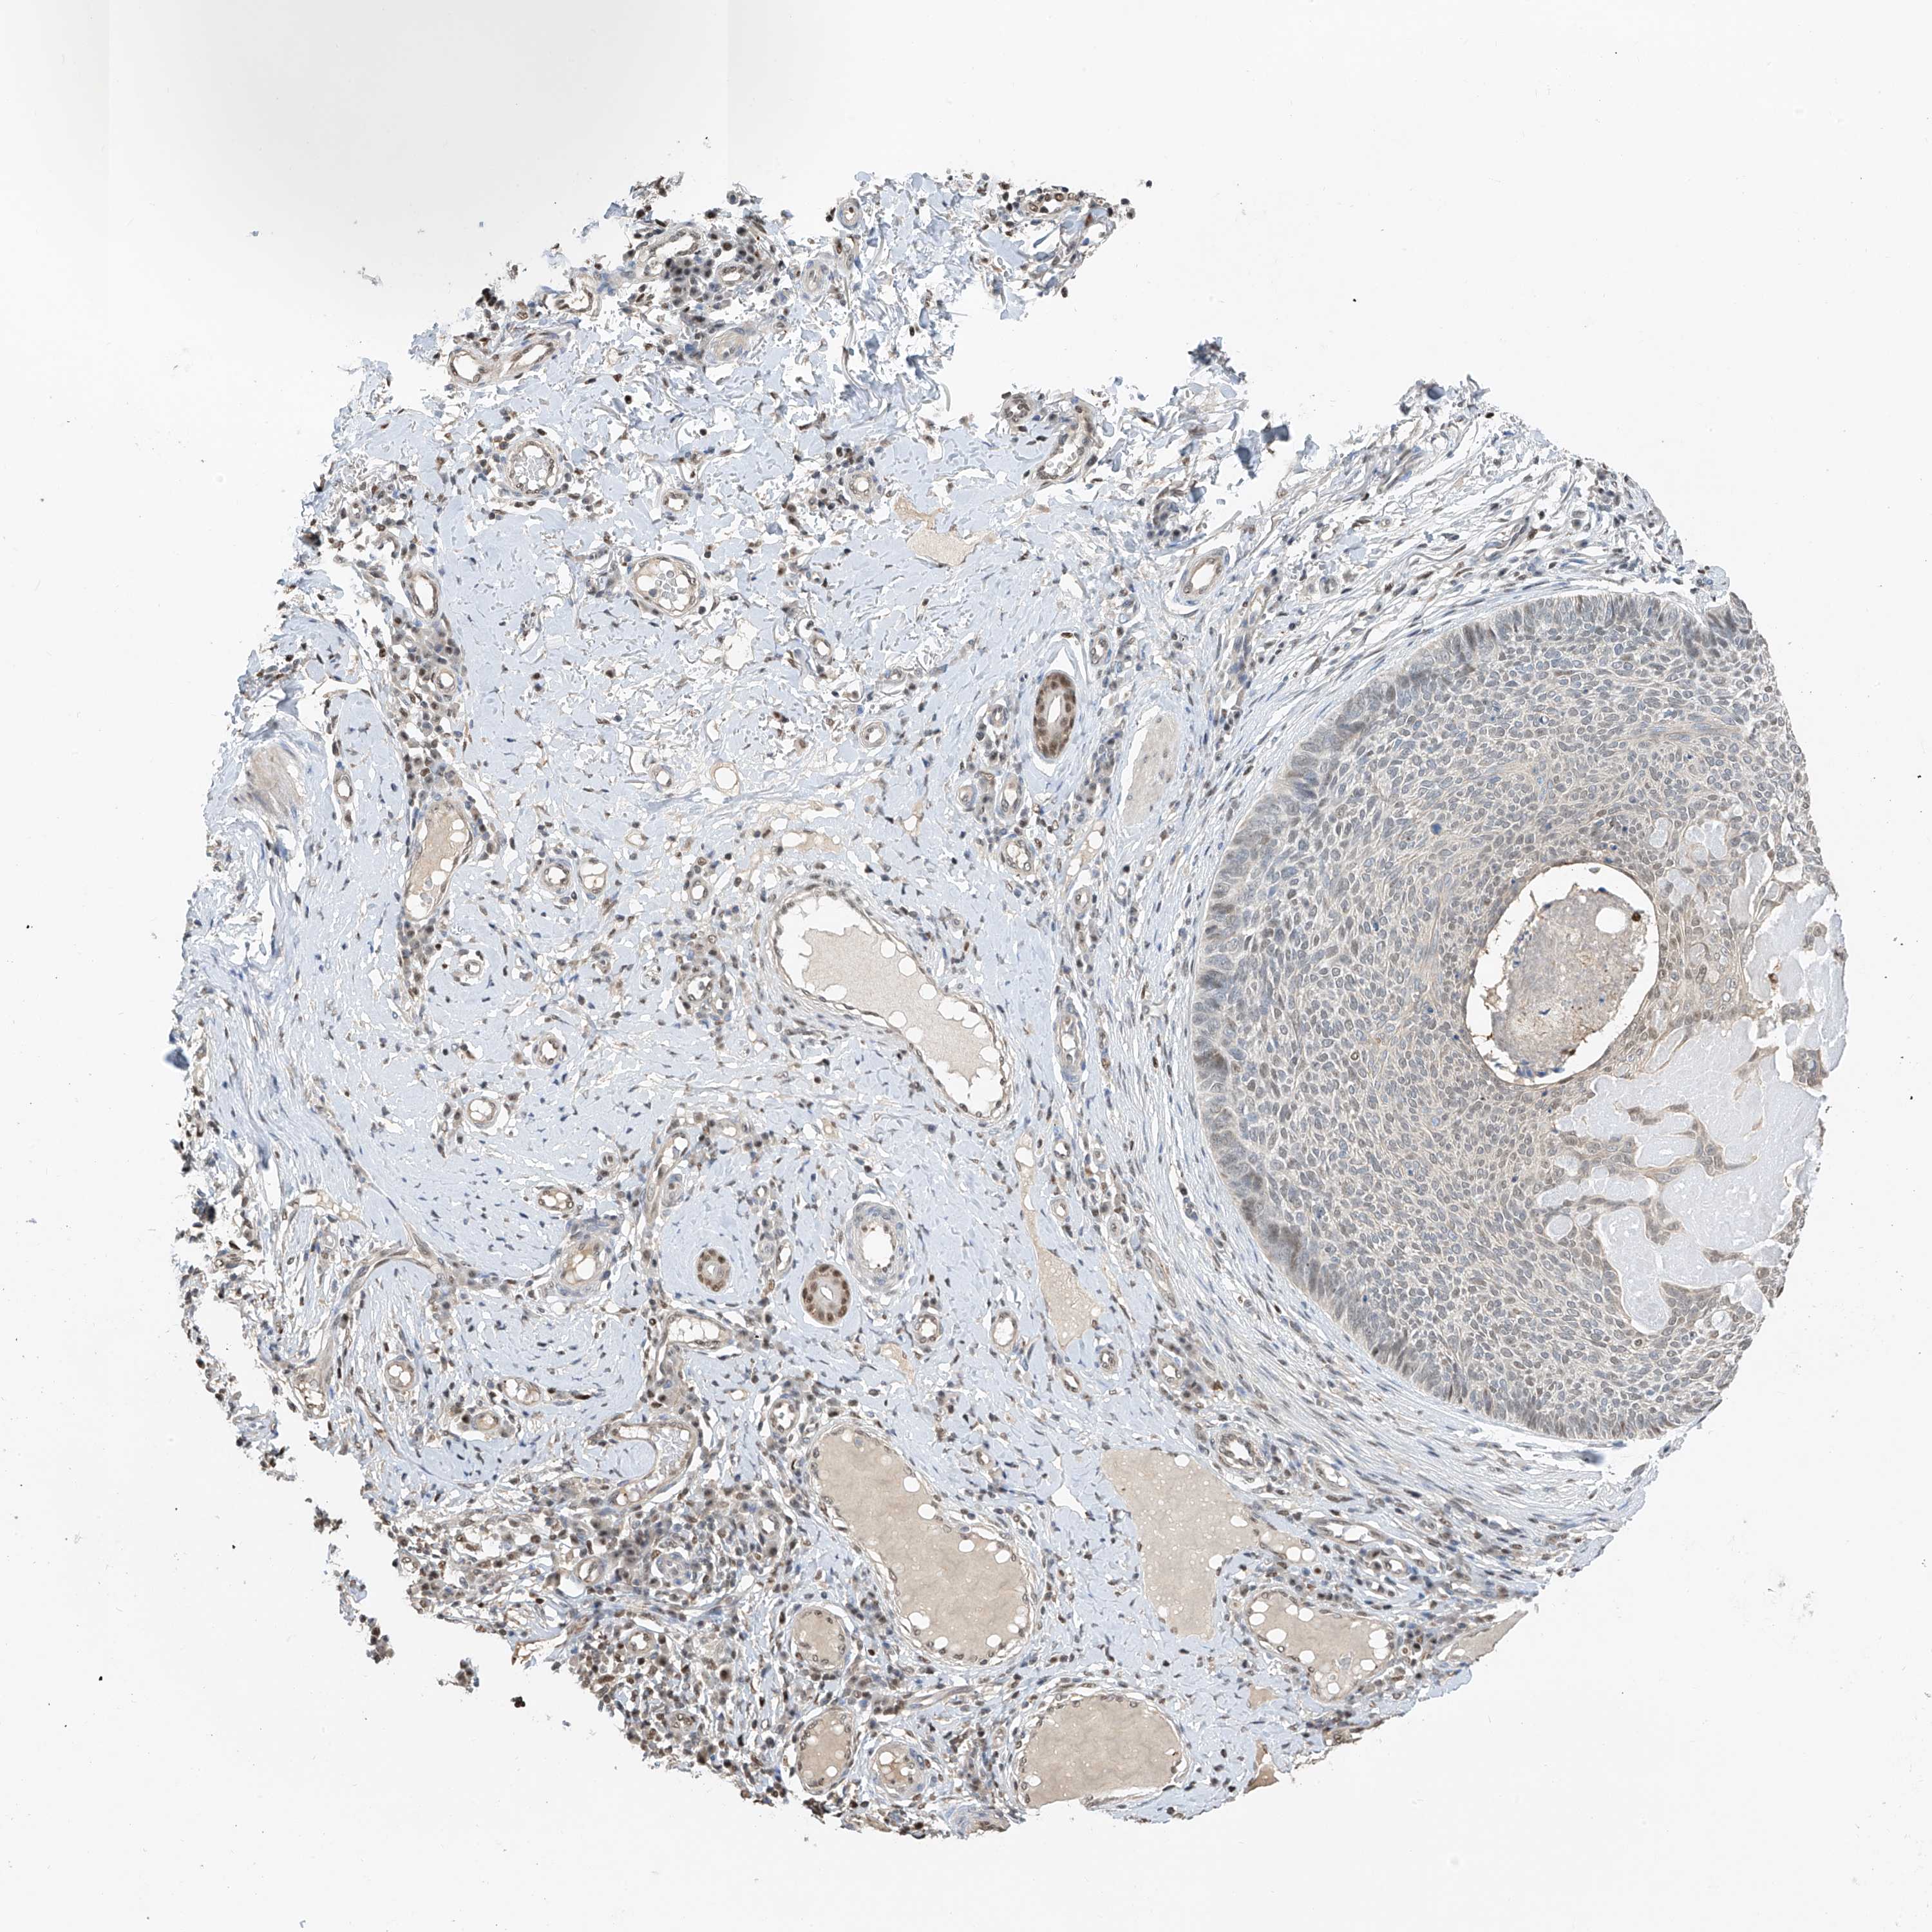

SKIN CANCER - Protein expressioni

A mouse-over function shows sample information and annotation data. Click on an image to view it in a full screen mode. Samples can be filtered based on level of antibody staining by selecting one or several of the following categories: high, medium, low and not detected. The assay and annotation is described here.

Antibody stainingi

Antibody staining in the annotated cell types in the current human tissue is reported as not detected, low, medium, or high, based on conventional immunohistochemistry profiling in selected tissues. This score is based on the combination of the staining intensity and fraction of stained cells.

Each image is clickable and will lead to virtual microscopy that enables deeper exploration of all samples and also displays staining intensity scores, fraction scores and subcellular localization as well as patient and tissue information for each sample.

Antibody HPA030712

Staining

High

Medium

Low

Not detected

Intensity

Strong

Moderate

Weak

Negative

Quantity

>75%

75%-25%

<25%

None

Location

Nuclear

Cytoplasmic/membranous

Cytoplasmic/membranous,nuclear

Basal cell carcinoma